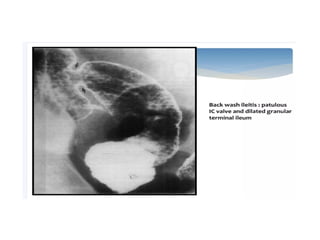

Ulcerative Colitis • Ulcerativecolitis (UC) is a characterized by superficial inflammation involving the colon. • The colonic involvement in UC is symmetric and contiguous. • Rectum is involved in almost all cases with varying length of proximal colonic involvement sometimes involving the entire colon (pancolitis) • Occasionally, terminal ileum can be affected and becomes edematous and dilated when the entire colon is involved and is called backwash ileitis

• Lead pipesign in chronic UC. Barium study images (A and B) of a patient with ulcerative colitis showing diffuse luminal narrowing and loss of haustrations (thin arrow) involving the entire colon without any skip areas. This featureless appearance of colon in chronic UC is known as lead pipe sign.